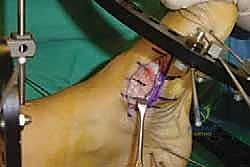

2. الشق الجراحي والوصول للمفاصل

يتم عمل شق جراحي واحد أو شقين (أحدهما في الجزء العلوي الداخلي والآخر في الجزء الخارجي) للوصول إلى مفاصل منتصف القدم دون الإضرار بالأوتار الحيوية والأعصاب والأوعية الدموية. يتم استخدام تقنيات الجراحة الدقيقة (Microsurgery) للحفاظ على الأنسجة المحيطة السليمة.

3. إزالة الغضاريف التالفة (Joint Preparation)

هذه هي الخطوة الأهم. يقوم الجراح بكحت وإزالة جميع الغضاريف المريضة والتالفة من بين العظام المراد دمجها. يجب الوصول إلى العظم الإسفنجي الصحي (Cancellous bone) الذي ينزف دماً، لأن هذا الدم يحتوي على الخلايا الجذعية وعوامل النمو الضرورية لعملية الالتحام (Fusion).